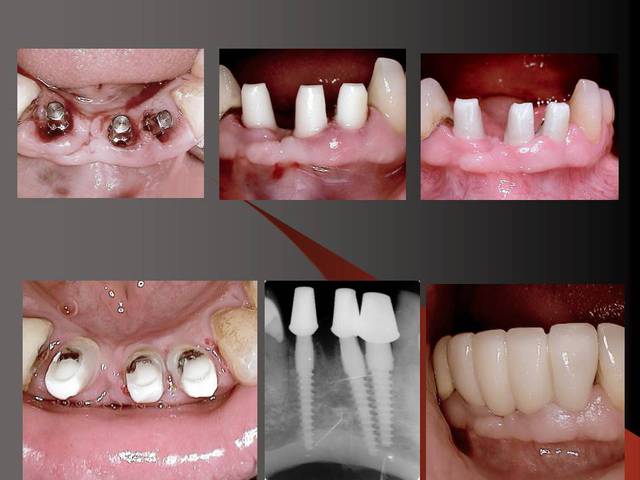

23 implants, rehabilitation totale

J'utilise la zircone depuis 7-8 ans,et je trouve que oui, la gencive est belle autour.

Par contre dans le dernier cas, je ne trouve pas que la gencive est belle, ell semble plutot inflammée...je crois que l'espace biologique n'est pas respecté.

Je trouve les implants sympas, mais pastrop l'aspect prothétique, mais c'est juste mon impression.

J´ai mis des photos pour mieux voir....

Merci pour ta remarque.C´est vrai que cela est mieux si on ne prérare pas ou presque pas les prep cap à cause des shippings . Normalement je ne les prépare pas, je choisis une forme (avec angle et longueur diiférents) selon le cas et ensuite je les cémente.

Sur la photo 5 on voit que je prépare surtout le titane de l´implant, le titane ne donne pas beaucoup du chaud quand il est préparé avec l´eau (pas comme aluminium par exemple).